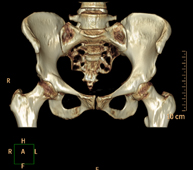

- TC Pelvis ósea

Exploración radiológica que mediante un sistema de rayos X y detectores que giran alrededor del paciente, reconstruyendo las imágenes por ordenador (TC Multidetector), permite el estudio de huesos, músculos y articulaciones de la pelvis.

- TC Caderas

Exploración radiológica que mediante un sistema de rayos X y detectores que giran alrededor del paciente, reconstruyendo las imágenes por ordenador (TC Multidetector), permite el estudio de huesos, músculos y articulaciones de la cadera.

- TC Sacroilíacas

Exploración radiológica que mediante un sistema de rayos X y detectores que giran alrededor del paciente, reconstruyendo las imágenes por ordenador (TC Multidetector), permite el estudio de las articulaciones sacroiliacas, y descartar enfermedades inflamatorias, traumáticas o degenerativas.